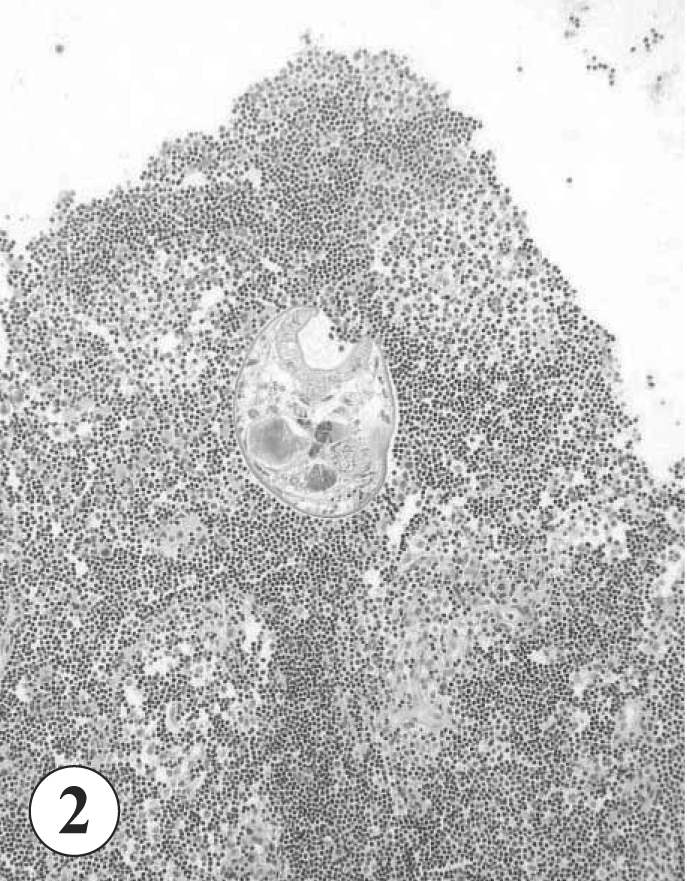

A case of colonic lymphoid tissue invasion by Gymnophalloides seoi in a Korean man

The Korean Journal of Parasitology 2006;44(1):87-89.